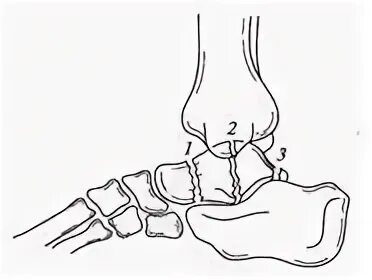

Перелом заднего